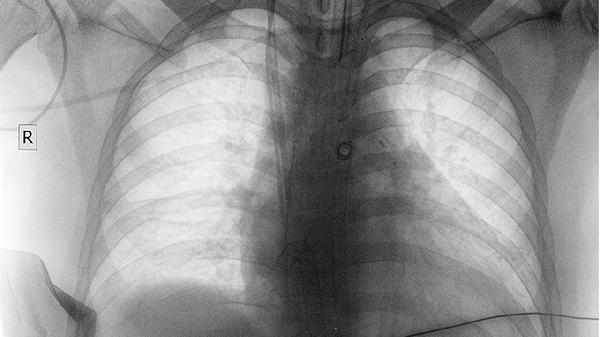

放疗对肺癌脑转移的控制机制主要通过高能射线破坏肿瘤细胞DNA结构,抑制其增殖能力。单发或寡转移灶患者接受立体定向放射外科治疗时,局部控制率较高,常见症状如头痛、肢体无力可得到缓解。全脑放疗适用于多发转移灶,能延缓颅内病灶增长,但可能伴随认知功能下降等副作用。治疗期间需定期复查头颅MRI评估疗效,若发现新发病灶可考虑追加放疗或更换治疗方案。

部分患者可能出现放疗抵抗现象,尤其存在特定基因突变时,肿瘤细胞对射线敏感性降低。这种情况下病灶可能在放疗后3-6个月内重新进展,表现为原有神经症状加重或新发定位体征。此时需要重新进行病理活检和基因检测,调整治疗方案。对于软脑膜转移等特殊类型,单纯放疗效果有限,往往需要联合鞘内化疗。